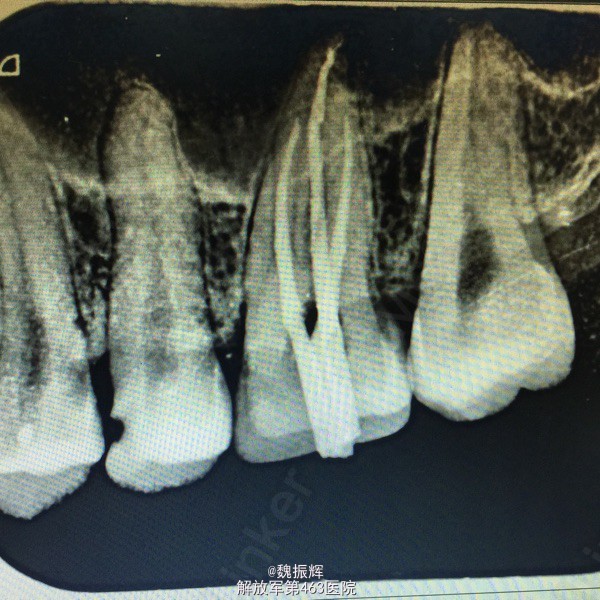

患者男性,23岁,左上后牙食物嵌塞痛数周,近日有自发痛夜间痛表现。影响进食,睡眠。来院就诊。

26的近中龋坏,探(+),冷(+),叩(-),X线示龋坏近髓达髓角。

诊断:26牙髓炎 处理:局麻下,26调合,去腐,开髓,拔髓,疏通根管,根管预备,根管冲洗,行一次性根管充填,氧化锌暂封。观察准备嵌体修复。